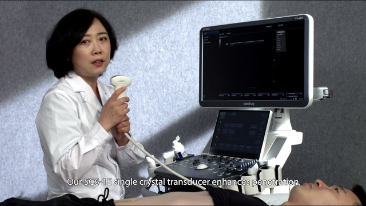

Opieka oparta mniej na stetoskopie, a bardziej na USG?

Zoptymalizowane schematy post?powania w badaniach ginekologicno-po?o?niczych s? niezb?dne, aby obs?u?y? du?? liczb? wizyt przesiewowych w poradniach zdrowia dla kobiet. Dla przyk?adu deformacje o?rodkowego uk?adu nerwowego (OUN) to jedne z najcz?stszych wad wrodzonych. Ze wzgl?du na r├│?ne warunki obrazowania, takie jak niewystarczaj?co dobra pozycja p?odu, obrazowanie ?rodkowej p?aszczyzny strza?kowej (MSP, median sagittal plane) jest szczeg├│lnie trudno uzyska? na podstawie klasycznego obrazu USG 2D. Dlatego automatyczne wykrywanie i pomiary mog? znacz?co poprawi? efektywno?? skanowania.